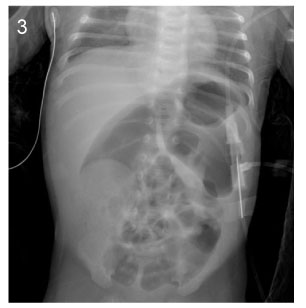

Fig. 3

Image of simple X-ray at the age of 43days (Case No. 4).

Fig. 3 Image of simple X-ray at the age of 43days (Case No. 4).